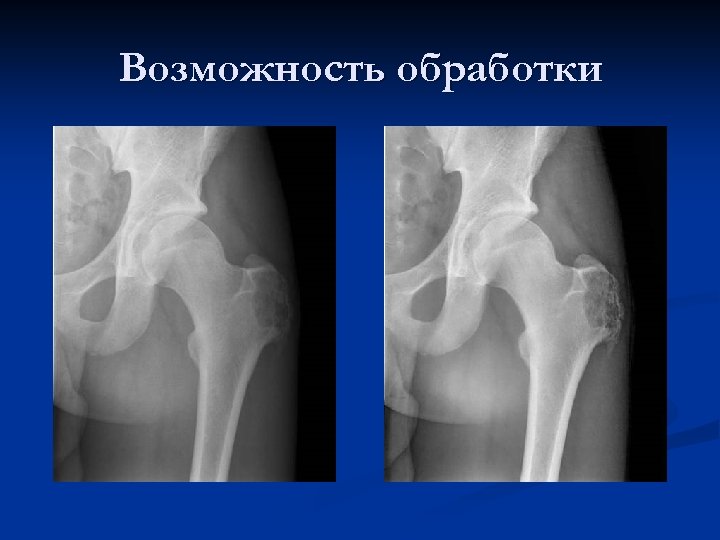

Возможность обработки